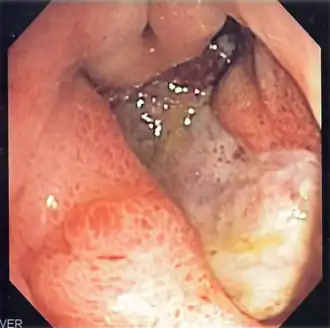

Indigo carmine staining (stomach)